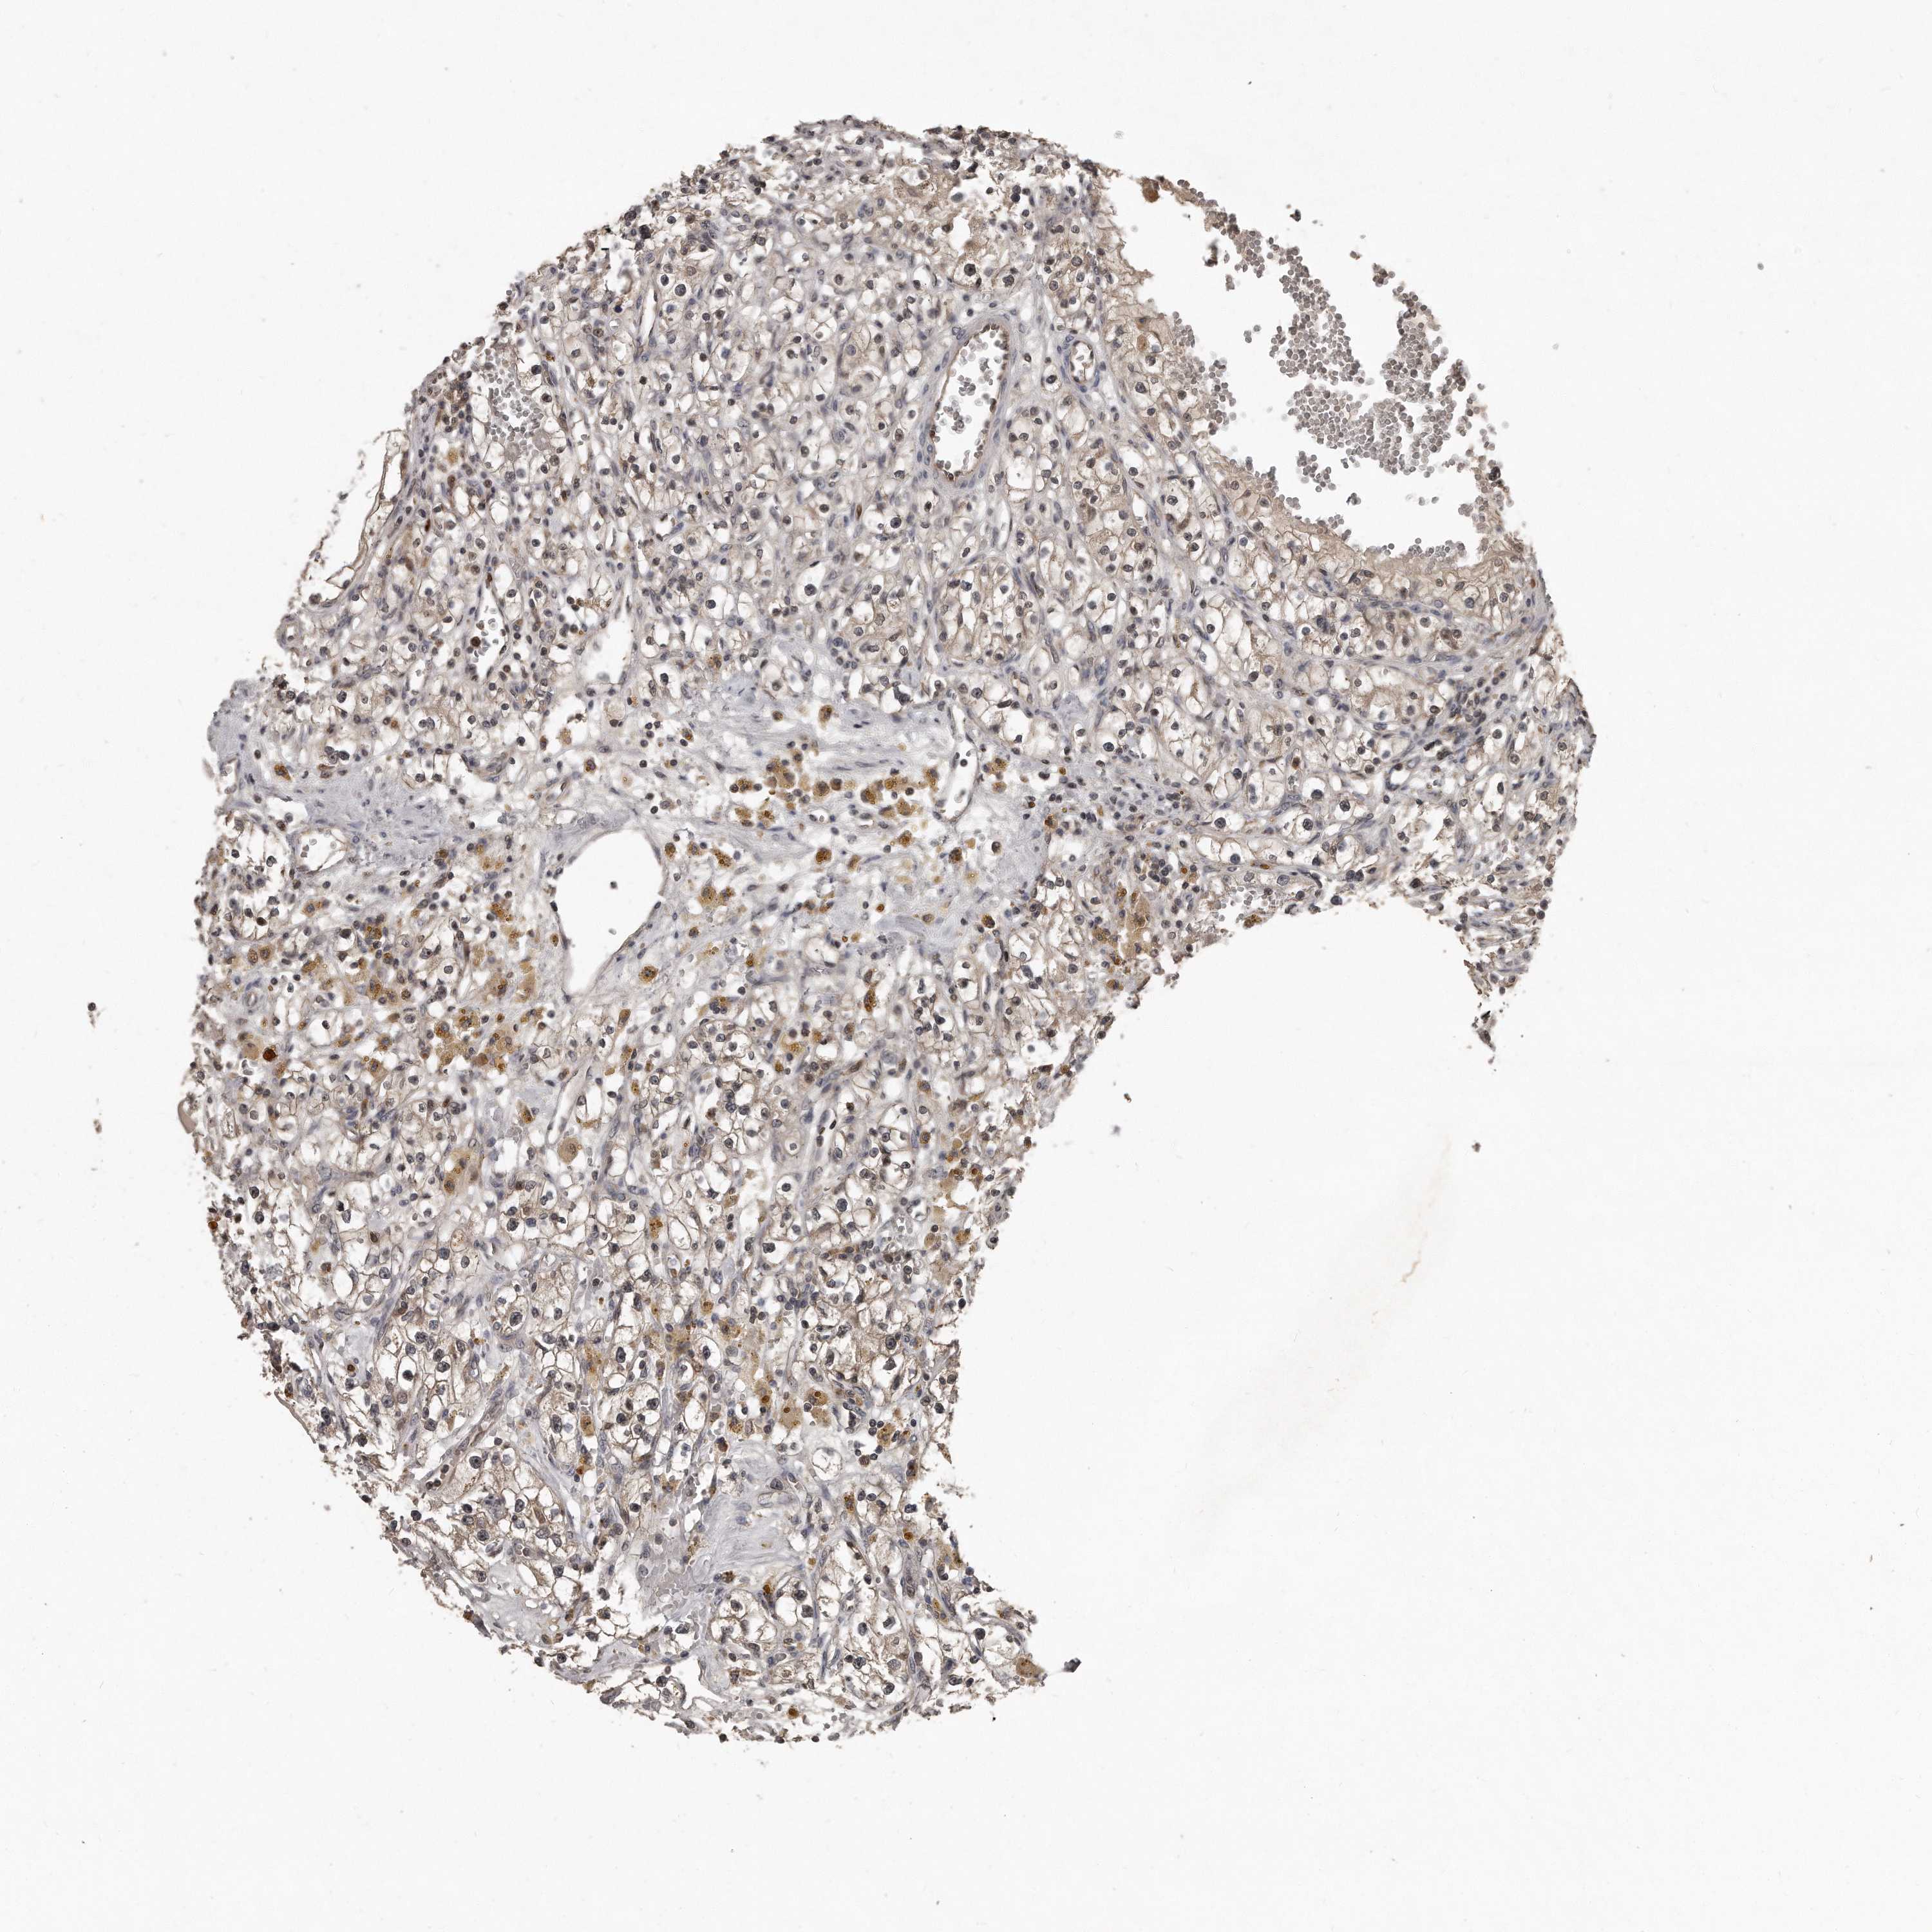

KIDNEY RENAL PAPILLARY CELL CARCINOMA (TCGA) - Interactive survival scatter ploti

The Survival Scatter plot shows the clinical status (i.e. dead or alive) for all individuals in the patient cohort, based on the same data that underlies the corresponding Kaplan-Meier plots. Patients that are alive at last time for follow-up are shown in blue and patients who have died during the study are shown in red.

The x-axis shows the expression levels (FPKM) of the investigated gene in the tumor tissue at the time of diagnosis. The y-axis shows the follow-up time after diagnosis (years). Both axes are complimented with kernel density curves demonstrating the data density over the axes. The top density plot shows the expression levels (FPKM) distribution among dead (red) and alive patients (blue). The right density plot shows the data density of the survived years of dead patients with high and low expression levels respectively, stratified using the cutoff indicated by the vertical dashed line through the Survival Scatter plot. This cutoff is automatically defined based on the FPKM cutoff that minimizes the p-score. The cutoff can be changed by dragging the vertical line or by entering a cutoff value in the square labeled "Current cut-off".

Under the Survival Scatter plot the p-score landscape (black curve; left axis) is shown together with dead median separation (red curve; right axis). Dead median separation is the difference in median mRNA expression between patients who have died with high and low expression, respectively. It is calculated as follows: median FPKM expression of dead patients with high expression - median FPKM expression of dead patients with low expression. This is intended to aid the user in visually exploring custom cutoffs and the associated p-scores and dead median separation.

Individual patient data is displayed and can be filtered by clicking on one or more of the category buttons on the top of the page. Categories describing expression level and patient information include: high, low, alive, dead, female, male and tumor stages. The scale of the x-axis can be toggled between linear and log-scale by clicking on the "x log" button. Mouse-over function shows TCGA ID, patient information and mRNA expression (FPKM) for each patient.

& Survival analysisi

Kaplan-Meier plots summarize results from analysis of correlation between mRNA expression level and patient survival. Patients were divided based on level of expression into one of the two groups "low" (under cut off) or "high" (over cut off). X-axis shows time for survival (years) and y-axis shows the probability of survival, where 1.0 corresponds to 100 percent.

GCH1 is not prognostic in Kidney Renal Papillary Cell Carcinoma (TCGA)

Best expression cut offi

Based on the FPKM value of each gene, patients were classified into two groups and association between prognosis (survival) and gene expression (FPKM) was examined. The best expression cut-off refers the FPKM value that yields maximal difference with regard to survival between the two groups at the lowest log-rank P-value. Best expression cut-off was selected based on survival analysis .

When clicking on this number, the vertical dashed line indicating cut-off, the interactive survival plot, and the Kaplan-Meier curve will be adjusted to show results based on the best expression cut-off.

: 0.44